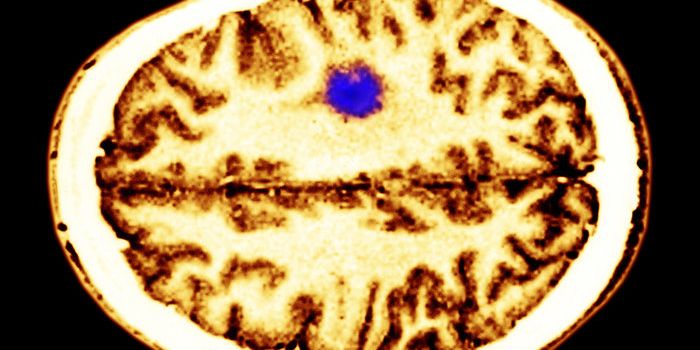

APR 24, 2015CancerThe simple act of thinking can accelerate the growth of many brain tumors.That's the conclusion of a paper in Cell publi ...

MAR 18, 2016Health & MedicineScientists have developed a brain implant that can turn the patient’s immune system against Alzheimer’s dise ...